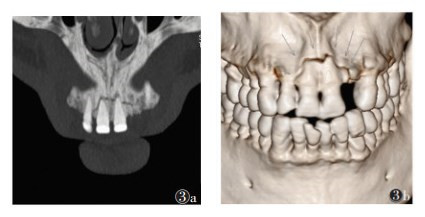

2 结果28例共49颗牙齿根折(图 1),其中单颗牙根折18例(64.3%),多颗牙根折10例(35.7%);中切牙根折39颗(79.6%),侧切牙根折10颗(20.4%);8例合并冠折;9例合并邻近牙槽突骨折;10例合并邻牙损伤,其中6例为牙齿缺如,4例为冠折(图 2,3)。49颗根折牙齿中,骨折线位于根颈1/3处12颗(24.5%),根中1/3处6颗(12.2%),根尖1/3处31颗(63.3%),以根尖1/3处最常见(图 4,5)。

| 图 3 男,40岁 图3a,3b MIP及VR清晰显示11~12牙邻近牙槽突骨折情况(箭头) |